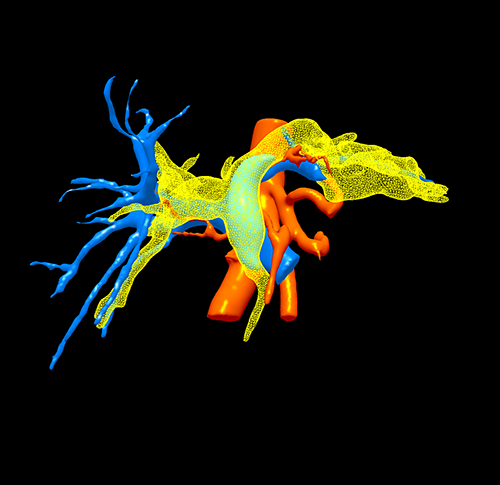

左肝癌并胆管癌栓---左半肝切除、胆管癌栓取出术